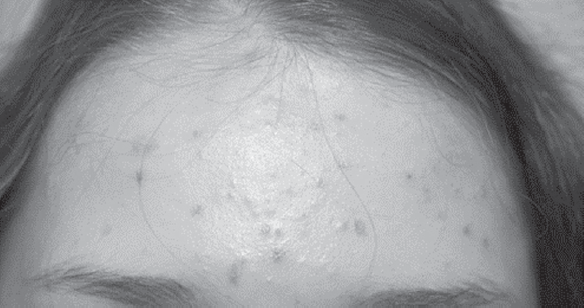

An increase in the number of patients with psychodermatological manifestations and the identification of a certain comorbidity during the course of diseases in patients with a dermatological profile makes us take a fresh look at this problem. Psychodermatology is one of the relevant and, at the same time, the least studied areas of modern medicine, which is at the junction of psychiatry and dermatovenereology. Psychiatry and psychotherapy studies the inner world of a person; Dermatovenerology deals with the diagnosis and treatment of diseases of the human skin and its appendages, and psychodermatology combines these two sections of medicine. In the modern world, as a result of increasing the amount of incoming sensory information, accelerating the rhythm of life, the action of harmful environmental factors, a person can be subjected to excessive psycho-emotional stress, leading to the development of mental disorders. Often it is skin rashes that are an objective manifestation of such disorders. Early diagnosis of psychodermatosis and signs of obsessive-compulsive pathology in sick people contributes to the timely identification of the category of people at risk of psychotic reactions and mental illness. This is especially true for young patients. Against the background of hormonal changes in the body, the crisis of adolescence, the increased educational load on them at school, the destroyed institute of family and marriage, an overabundance of sensory information and physical inactivity, the incidence of psychodermatosis throughout the world, including in our country, is increasing.